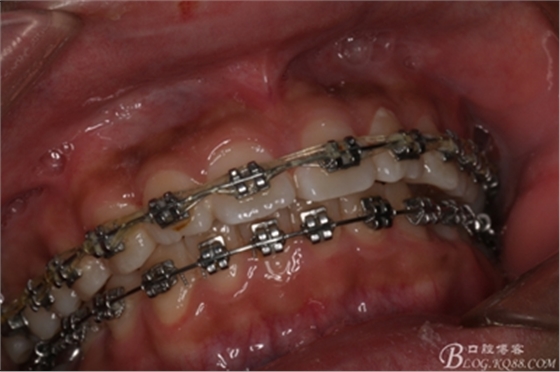

圖2.術(shù)前的口內(nèi)閉口位照片:上下牙列基本整齊